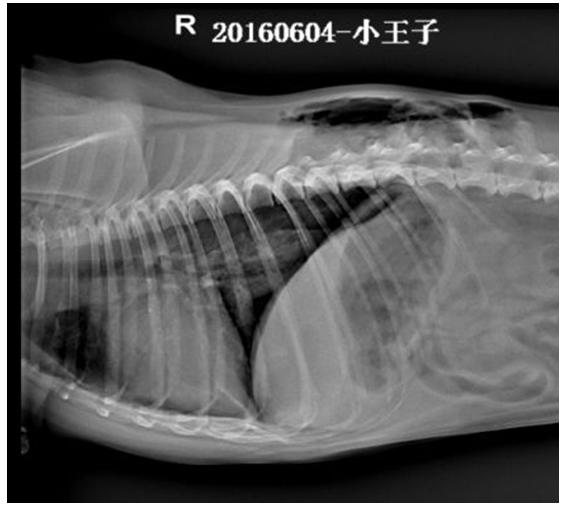

X线检查所示,右侧卧片可见,T9至L3之间背部皮下积气,肺脏萎缩,膈三角区密度降低,积气;仰卧位可见, T6至L3左侧胸部皮下气肿,右侧T8至L2右侧胸部皮下气肿,右侧膈角尖锐,密度降低,积气,提示胸壁透创并发气胸。

3 分析诊断

结合临床症状及X片检查结果,初诊为胸壁透创并发气胸。